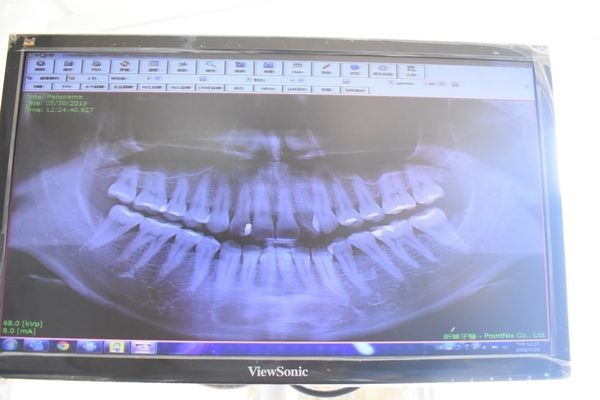

因為第一次看診

所以使用最新3D立體X光機進行掃描

讓醫師更了解我的牙齒狀況